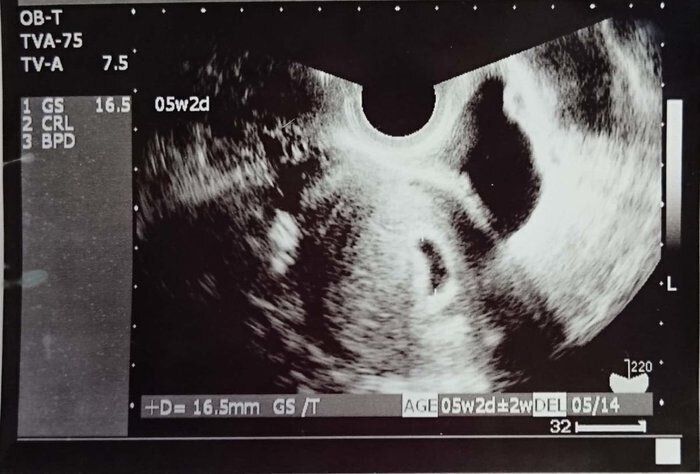

マダムまかろんさんの妊娠5週目のエコー写真 ようやく妊娠成立!

不妊治療専門クリニックで5回目の体外受精を行い、その後医師から妊娠していることを告げられました。妊娠5週目の画像です。当時は、妊娠したうれしさより、正直なところ「これでもうあの治療のつらさから解放されるかもしれない」という気持ちの方が強かったです。まだ流産の可能性が高いということで、夫も私も心から喜ぶことはできませんでした。